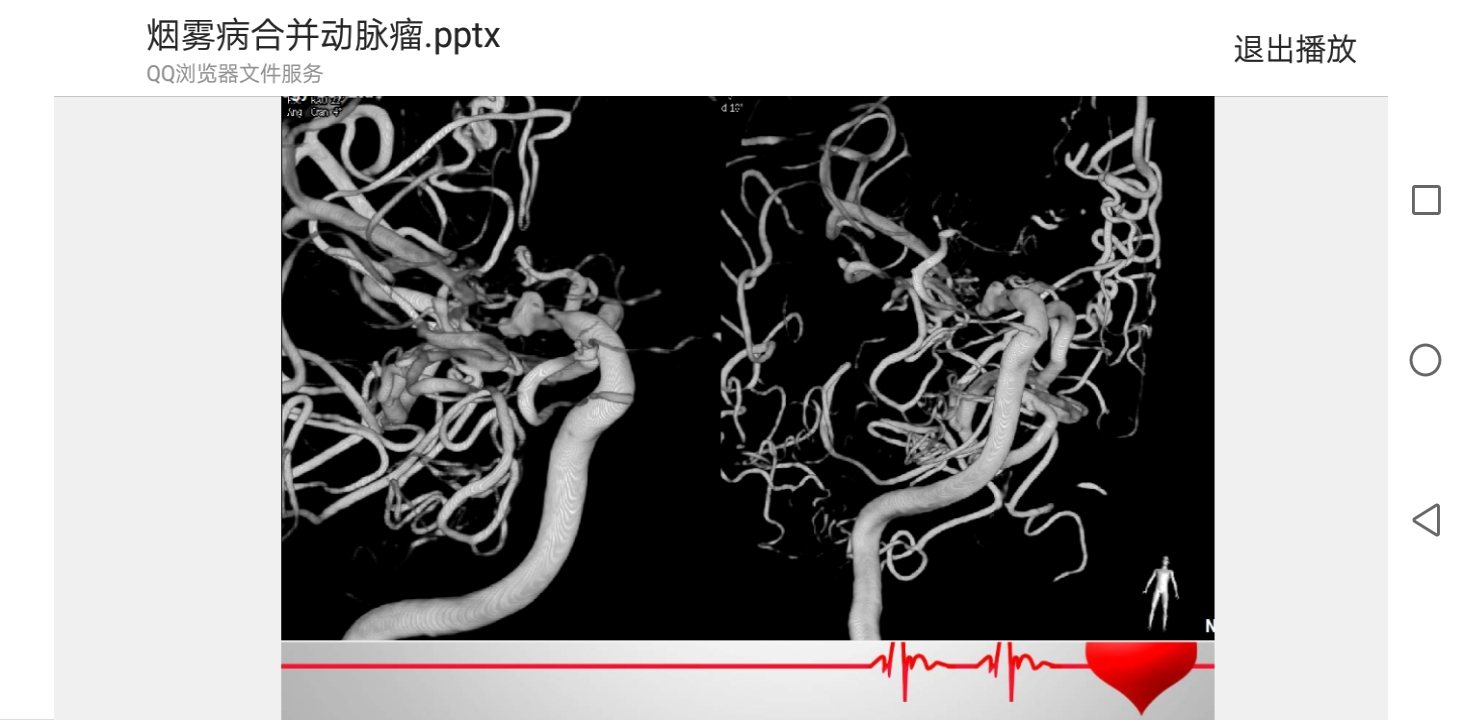

脑血管造影3D成像

脑血管造影3D成像